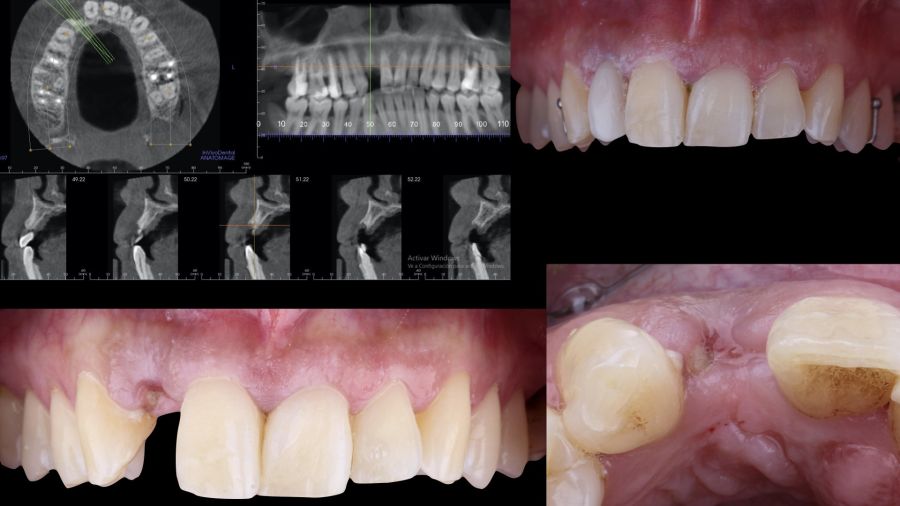

Una mujer de 29 años acudió a nuestra clínica dental tras sufrir un traumatismo en el incisivo lateral superior derecho (1.2). Tras el traumatismo, el diente sufrió una fractura de toda la corona anatómica, por lo tanto, solo presentaba un resto radicular en posición subgingival. El resto radicular se diagnosticó como no restaurable por lo que se valoraron detenidamente las opciones terapéuticas disponibles con la paciente. Se decidió reemplazar el diente 1.2 con un implante dental y se elaboró el siguiente plan de tratamiento y secuencia clínica; Fase I: extracción del resto radicular 1.2 y reconstrucción del proceso alveolar utilizando un procedimiento de preservación alveolar no invasivo. Restauración provisional inmediata mediante una prótesis parcial de acrílico removible. Fase II: colocación guiada de un implante y aumento de espesor mucoso mediante un injerto de tejido conectivo. Fase III: conformación y modelado del perfil de emergencia mediante una prótesis provisional directa a implante y restauración cerámica sobre implante definitiva.

-Fase I: se realizó la extracción atraumática del resto radicular 1.2 y se efectuó un legrado del tejido de granulación. A continuación, se realizó el relleno del alveolo mediante un injerto óseo bovino inorgánico (0,25-1mm) combinado con fibrina autóloga rica en plaquetas y leucocitos. Finalmente, se suturó aproximando los bordes mediante 4 puntos simples desde el margen mucoso vestibular al palatino. Después, la paciente siguió usando su prótesis parcial removible como restauración provisional (Figura 1).

-Fase II: la cicatrización transcurrió sin complicaciones. Tras 5 meses de la cirugía de preservación alveolar, se planificó la cirugía implantológica guiada en posición 1.2 (Figura 2). Para ello, se utilizaron un archivo DICOM procedente de la tomografía computarizada de haz cónico (CBCT) y el archivo STL procedente del escaneado mediante un escáner óptico intraoral. Con esta información se construyó una férula quirúrgica de soporte dental (Figura 3). La férula quirúrgica se ancló sobre los dientes y guió la realización del lecho implantario y la colocación del implante. La técnica quirúrgica de cirugía guiada consistió en una cirugía con colgajo, preparando e insertando el implante (3,5 x 11,5 mm) según el protocolo estandarizado de cirugía guiada Nobel Active® (Nobel Biocare AB, Gothenburg, Sweden). Una vez colocado el implante 1.2, se obtuvo un injerto gingival compuesto de epitelio y tejido conectivo de la mucosa masticatoria palatina. A continuación, se realizó la desepitelización de la capa superficial de dicho injerto fuera de boca mediante una hoja de bisturí 15C con la finalidad de obtener un injerto de tejido conectivo de la capa subyacente18.